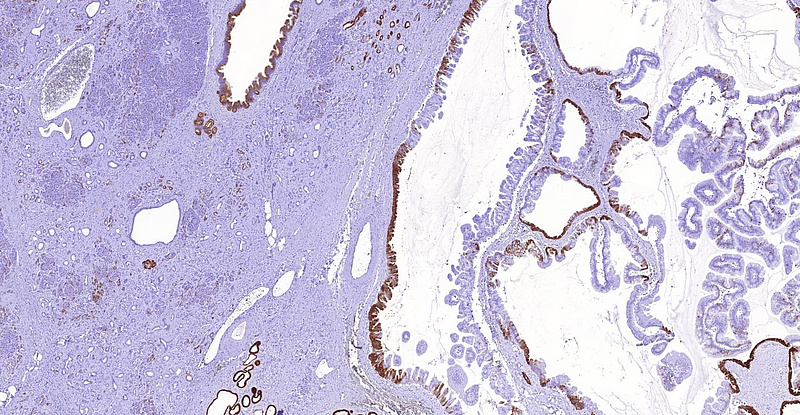

Immunohistochemistry demonstrated diffuse positivity for MUC5AC (Panel D). MUC6 was focally positive within the oncocytic component of the tumour (Panel E). Of note, intra- and interlobular fibrosis with remarkable atrophy of the acini was detected in the non-neoplastic area of the pancreas, mimicking well-differentiated (tubular) invasive carcinoma (Panel F). Endocrine cells were comparatively spared and the lobocentric architecture was preserved.